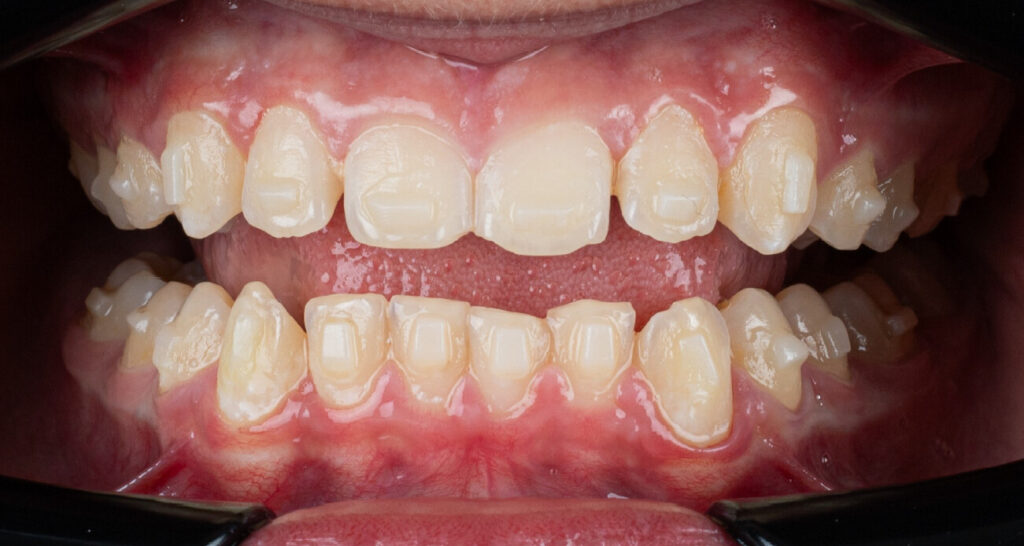

A 13-year-old male patient presented with a deep bite, characterized by near-complete coverage of the mandibular incisors. Clinical evaluation revealed bi-arch crowding, dental rotations, and proclination of the maxillary lateral incisors, contributing to the patient’s esthetic concerns. The facial profile was retrusive, consistent with mandibular retrognathism, and no significant periodontal abnormalities were detected.

The patient presented with a skeletal Class II relationship with bilateral molar and canine Class II and a Class II division 2 dental pattern. The deep bite was associated with anteroinferior crowding and an accentuated Curve of Spee. Facial analysis revealed good symmetry, a slightly increased lower facial third, and a convex profile characterized by mandibular and chin retrusion. Lip competence was mildly reduced, with a decreased nasolabial angle and mentalis hyperactivity, all of which compromised overall facial harmony.